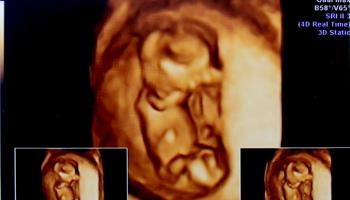

8. 임신 12주 차 - 2.88cm